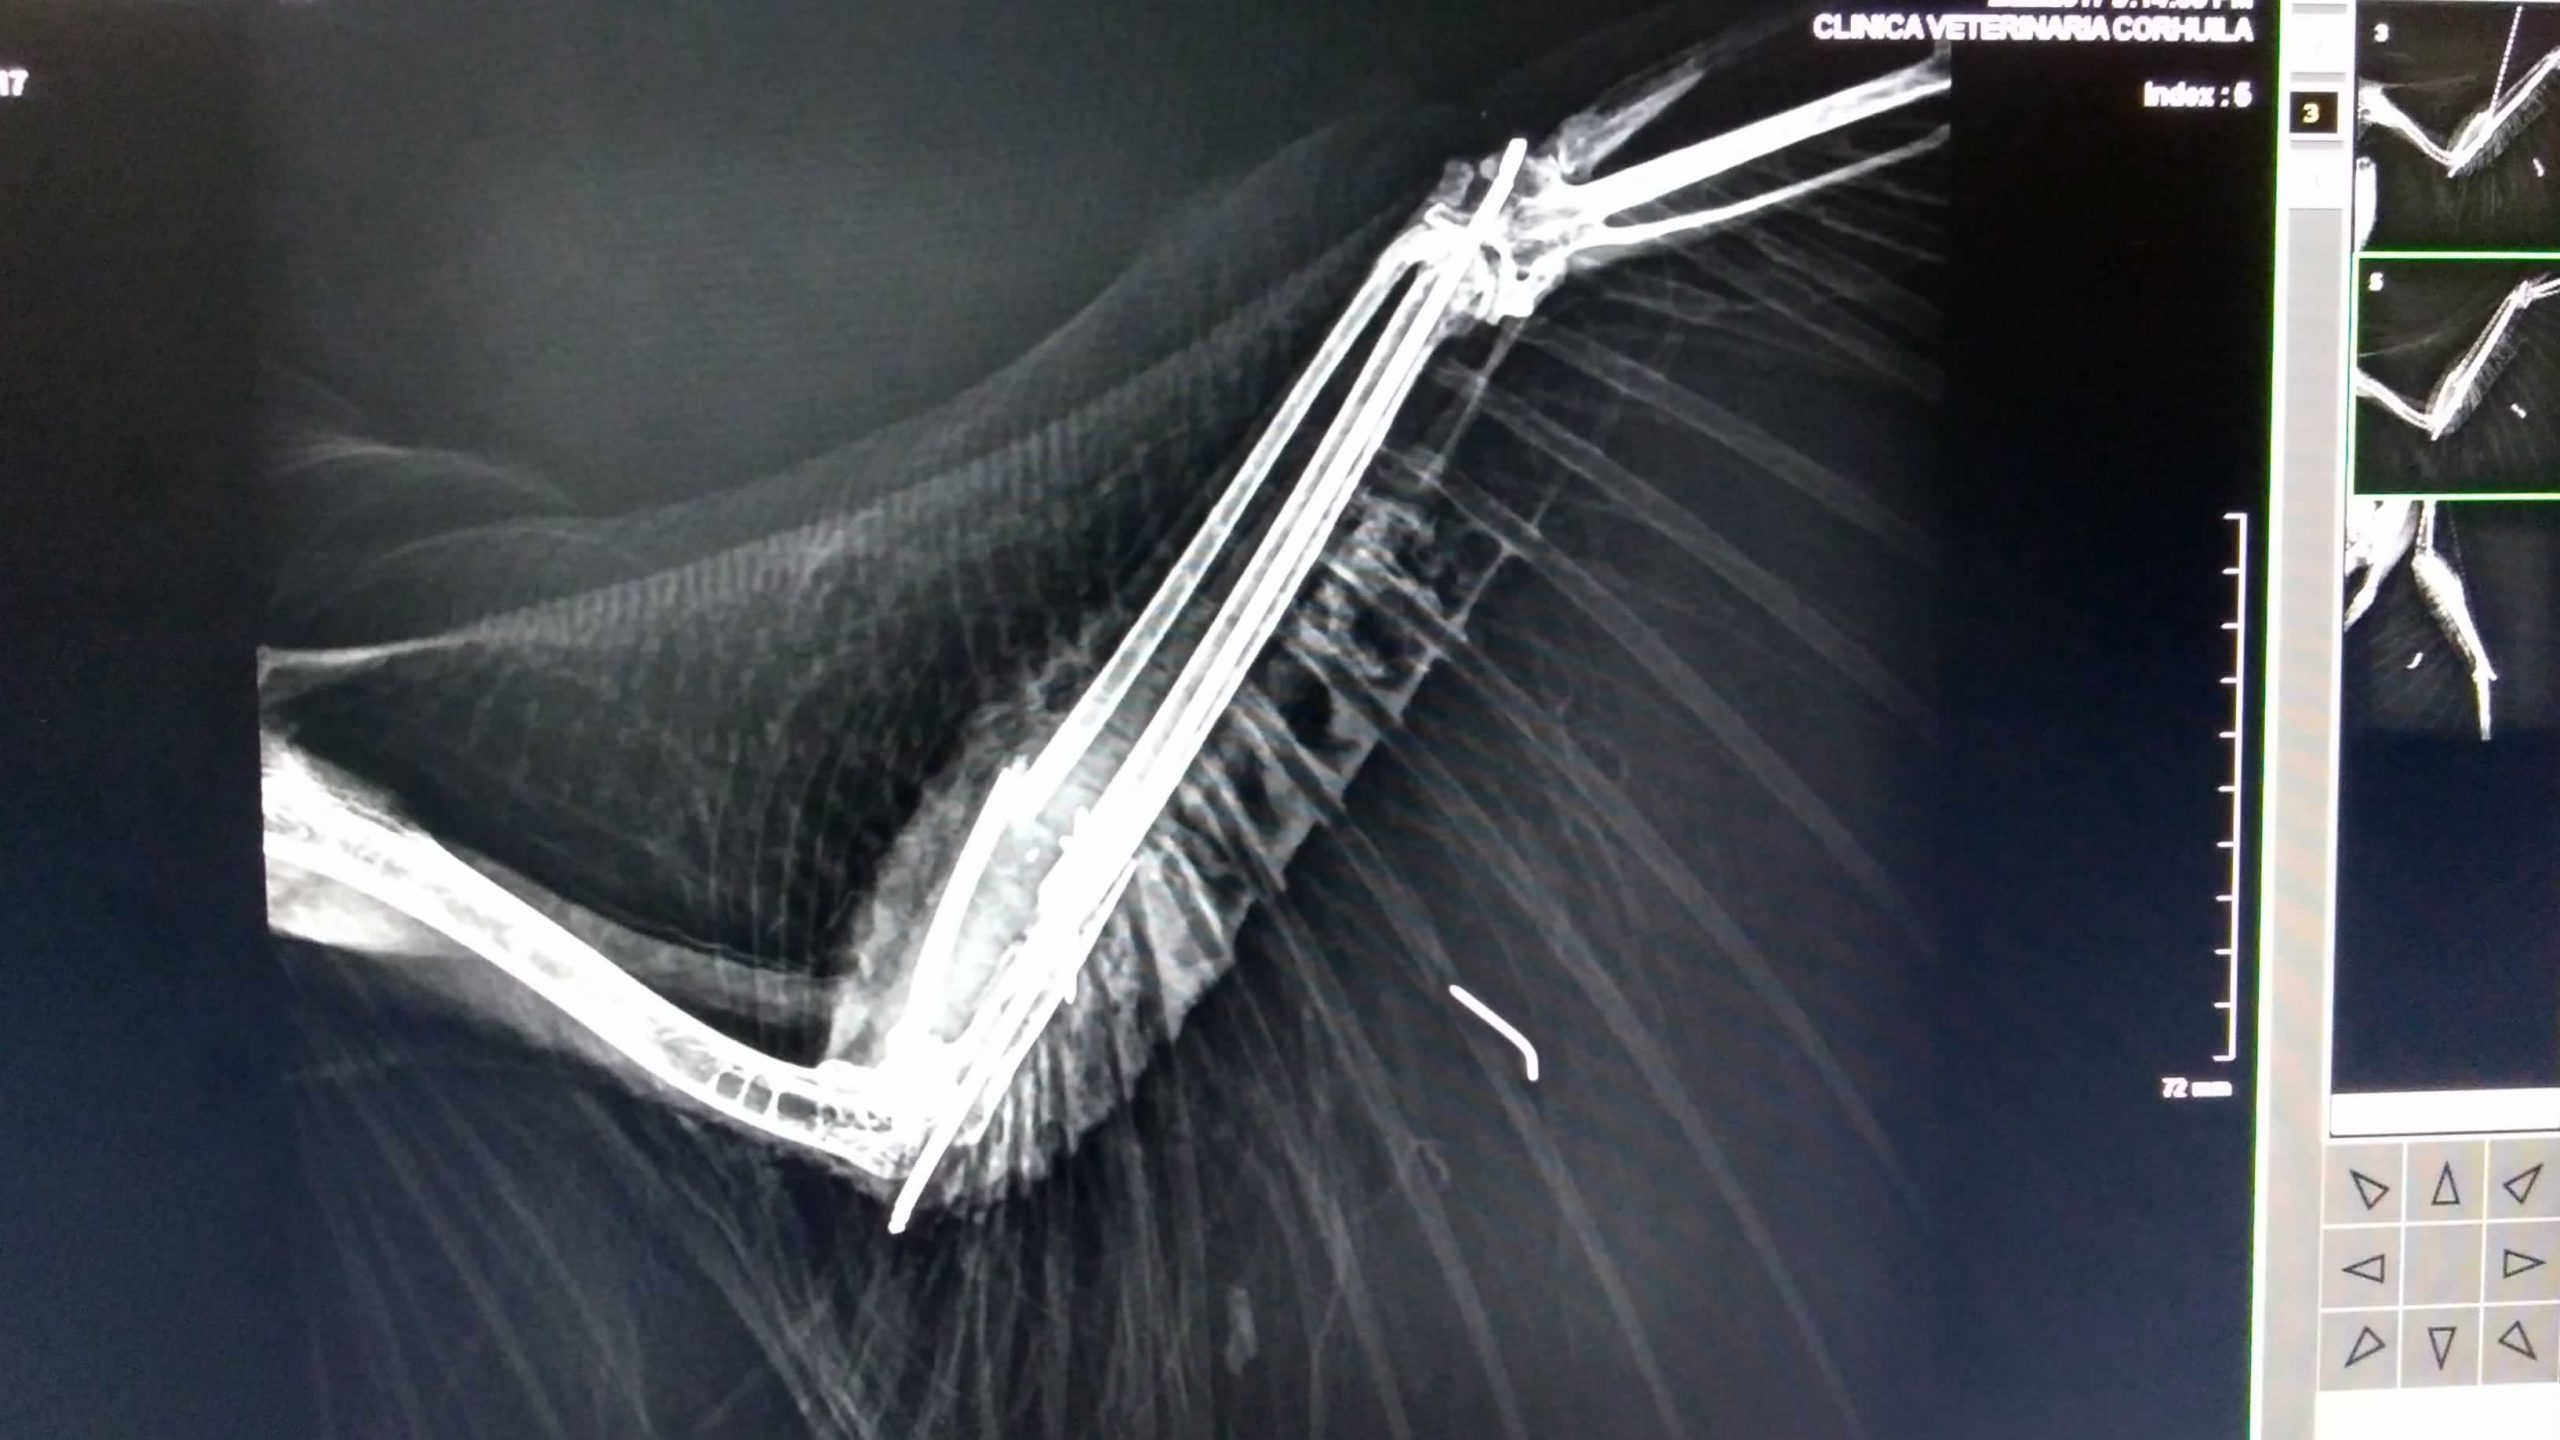

Esta ave ingresó al Centro de Atención y Valoración-CAV de Fauna Silvestre de la CAM gravemente herida en su ala izquierda. Luego de la valoración médica y la toma de radiografías, se evidenció que le habían disparado con perdigones.

Producto de este ataque, el águila presentaba varias fracturas en su extremidad alar y requirió ser intervenida quirúrgicamente, operación que se adelantó en conjunto entre la autoridad ambiental del Huila y la facultad de Medicina Veterinaria y Zootecnia de la universidad Corhuila.

“En el momento de la valoración que incluyó la toma de radiografías, los profesionales diagnosticaron que el ave presentaba cuatro impactos por perdigones en diferentes áreas de su cuerpo, y registraba una fractura cerrada de radio y cubito en su ala izquierda”, explicó Osiris Peralta Ardila, profesional de la CAM.